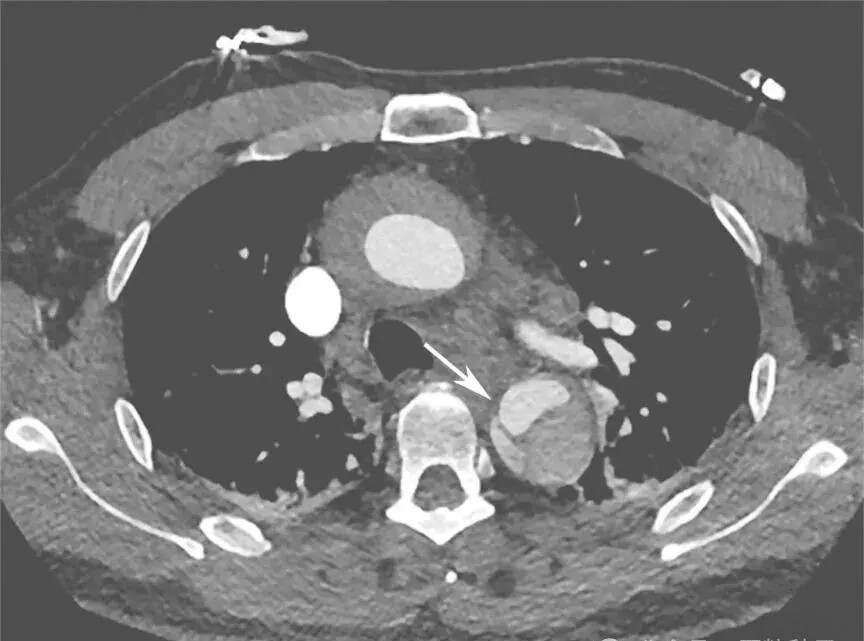

4.肺CT平扫

降主动脉瘤样扩张,直径较前有所增加,可见内膜移位,不除外主动脉夹层(图1)。

图1 肺部CT平扫(箭头处钙化点内移)